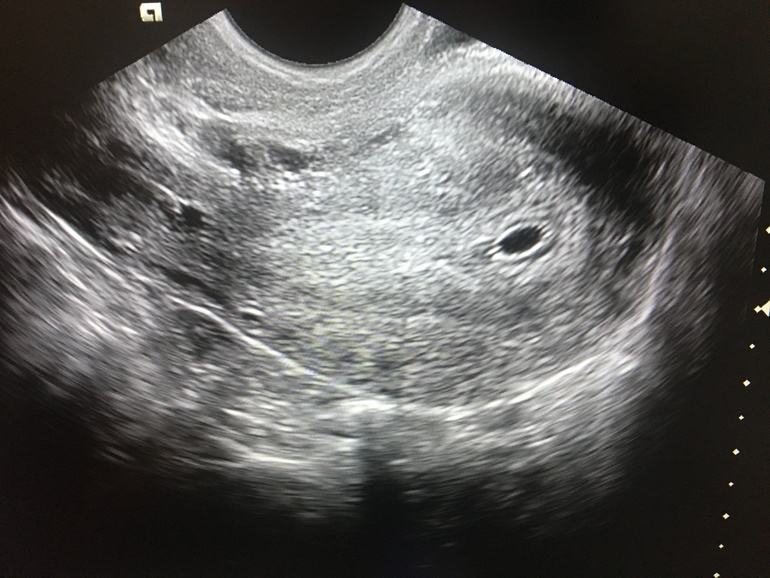

Сходила на узи, вместо спокойствия - еще больше вопросов(((

Вопросы про УЗИ, обследования и анализы: что, где, как, когда?Девочки, в общем сходила на узи. Беременность под вопросом.

Вообще узи без консультации было, поэтому и остаётся только читать да вглядываться. Меня смущает,что я вижу две чёткие точки...может ли это говорить о двойне?

Узи нельзя интерпретировать самостоятельно, все что мы там видим может оказаться чем угодно. Я вижу "точки" по всему фото, например. Но это ничего не значит. Написали одно включение, значит, наверное, одно. Жёлтое тело в одном яичнике. Значит возможны только близнецы. Очень редко когда два фолликула выходят из одного яичника.

Посмотрела в вашем профиле посты, у вас же тесты только недавно начали полосатится, рановато вы на узи пошли

Но две точки видно чётко😅😅😅